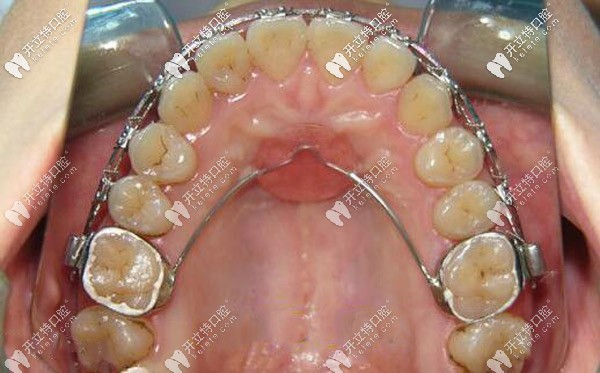

腭側(cè)nace弓矯正圖片▼

腭側(cè)nace弓矯正圖片